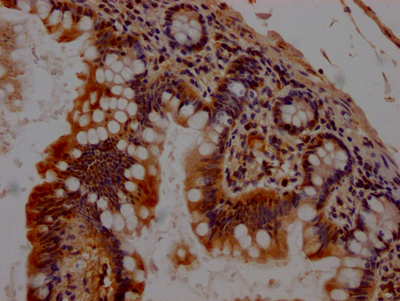

CSB-RA176809A0HU

IHC image of CSB-RA176809A0HU diluted at 1:100 and staining in paraffin-embedded human small intestine tissue performed on a Leica BondTM system. After dewaxing and hydration, antigen retrieval was mediated by high pressure in a citrate buffer (pH 6.0). Section was blocked with 10% normal goat serum 30min at RT. Then primary antibody (1% BSA) was incubated at 4℃ overnight. The primary is detected by a Goat anti-rabbit IgG polymer labeled by HRP and visualized using 0.05% DAB.